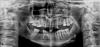

lisi4karu Опубликовано 13 апреля, 2011 Поделиться Опубликовано 13 апреля, 2011 Уважаемые доктора, подскажите пожалуйста!Хотелось бы поставить 2 имплантанта на верхнюю челюсть) Подскажите, нужно ли будет наращивание кости делать? И возможно ли это будет сделать во время имлантирования или до этого все же?Заранее спасибо!С уважением, Марина Ссылка на комментарий

Zborzh Опубликовано 13 апреля, 2011 Поделиться Опубликовано 13 апреля, 2011 К сожалению, я не в Москве, не уверенна ,что у нас КТ можно найти. Т.е по снимку вообще ничего сказать нельзя?По снимку сказать что-то можно , но уверенности нет ...если нет КТ, то только методом "тыка" при сверлении ... провалимся в пазуху или нет ... Если провалятся , то , либо сразу надо идти на открытый синус-лифтинг, либо , ушиться , назначить соответствующую терапию , и потом все равно пойти на открытый синус ( при выборе имплантации , как лечения ) , либо , выбирать другие варианты лечения.. Ссылка на комментарий

Bier Опубликовано 14 апреля, 2011 Поделиться Опубликовано 14 апреля, 2011 синуслифтинг вам потребуется на 99% делать мост, обрабатывая клык, я бы не стал, если есть возможность поставить имплантаты. пазуху можно пропальпировать или вообще увидеть глазами, откинув лоскут. Делать "диагностические сверления" на мой взгляд не очень оправдано. Ссылка на комментарий